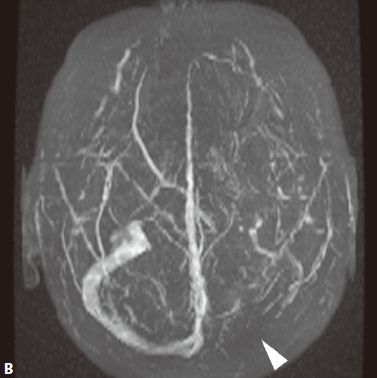

- MRA可直接显示颈内动脉、大脑前、中动脉狭窄或闭塞,于颅底见烟雾状异常血管网,常可见到颈外动脉和椎-基底动脉分支代偿性增粗。

又称为脑底异常血管网症、脑底动脉环闭塞症。是以脑内虹吸段至大脑前、中动脉近端狭窄或闭塞,同时伴有广泛侧支循环形成,导致颅底出现异常毛细血管网为特征的脑血管病。好发年龄10岁以下和40-50岁。临床表现为脑缺血和脑出血两大类。儿童多为颈内动脉系统缺血性改变,成人多为颅内出血。

- MRI表现为脑缺血引起的T1WI低、T2WI高信号脑梗死区,颈内动脉及大脑中动脉主干的“流空效应”变弱或消失,异常血管网在T2WI上表现为基底节区和鞍上池内多发细小血管影,呈网状低信号或无信号区。皮质侧支循环形成时,增强扫描可见皮质血管增多、扩张、强化、呈“常春藤征”。